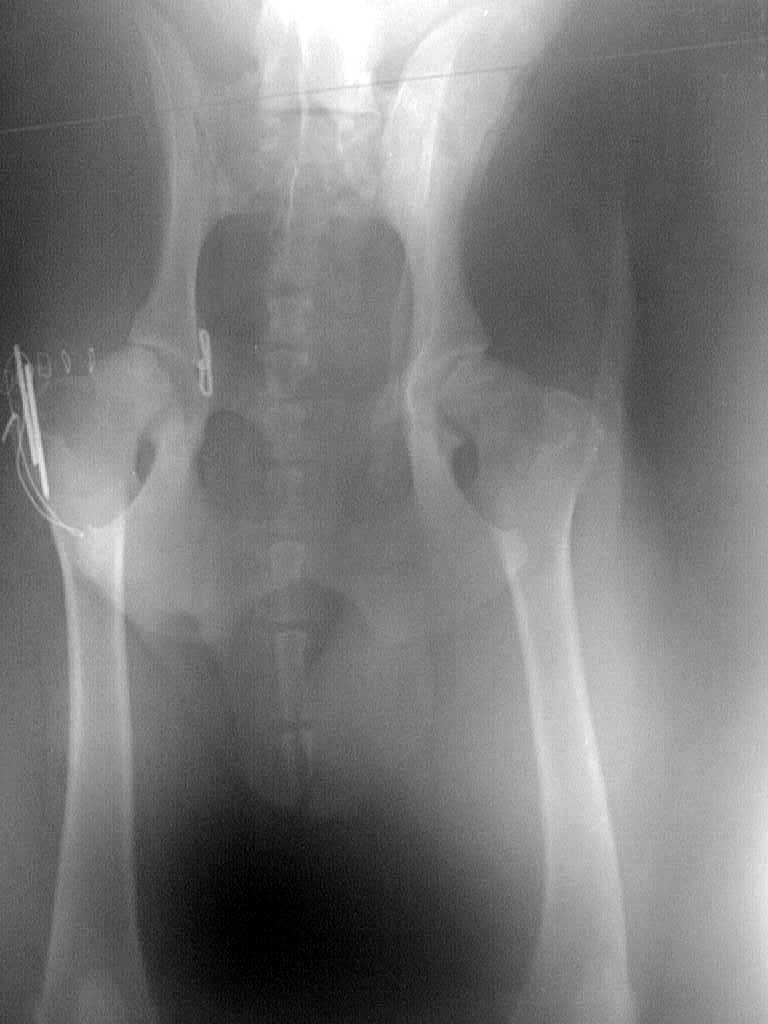

Beckenfaktur

Plattenrekonstruktion

Hüftgelenksluxation

Bohrdraht-Fixation